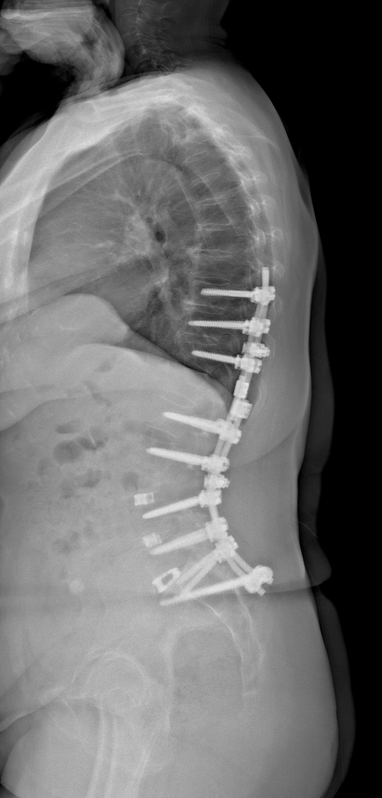

• Σπονδυλοδεσία: Σε περιπτώσεις αστάθειας της σπονδυλικής στήλης, χρησιμοποιείται η σπονδυλοδεσία για να σταθεροποιηθεί η σπονδυλική στήλη.

Μεταλλικές βίδες και ράβδοι χρησιμοποιούνται για να συνδέσουν τους σπονδύλους, ενώ μπορεί να τοποθετηθούν οστικά μοσχεύματα για να

ενθαρρύνουν τη σύντηξη των σπονδύλων